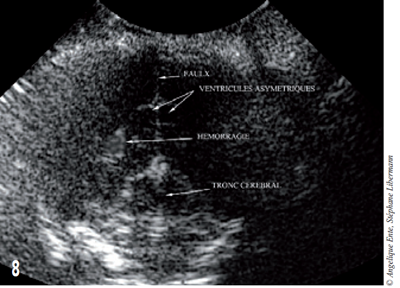

Les ventricules sont symétriques et de taille normale. Une lésion focale peu étendue, dont l’échogénicité évoque une hémorragie intra-parenchymateuse, est visible en partie ventrale du lobe temporal gauche (figure 8).

Figure 8 – Visualisation par échographie de l’encéphale. L’asymétrie ventriculaire est discrète et résulte de l’effet de masse créé par l’hémorragie.